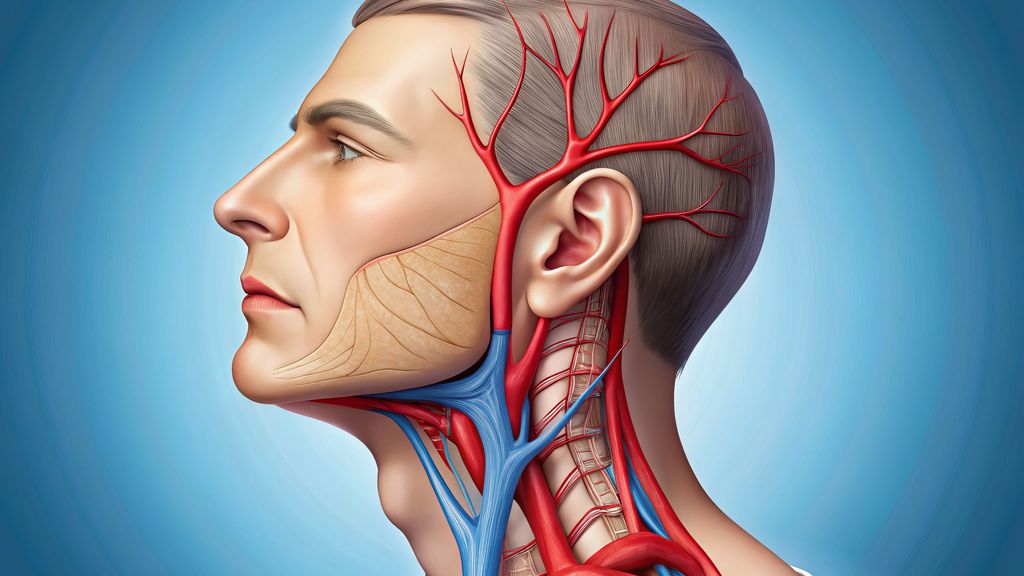

Anatomie

In der vorderen Halsregion liegt die A. carotis communis, diedem Aortenbogen (links) bzw. dem Truncus brachiocephalicus (rechts) entspringt. Sie teilt sich typischerweise auf Höhe des dritten bis vierten Halswirbels in die zwei wichtigsten Endäste für die Versorgung von Kopf und Hals. Bei dieser Gabelung befindet sich der Bulbus caroticus als Teil des sinuaortalen Systems. Etwas 2–3cm distal des Bulbus befindet sich die typische extrakranielle Lokalisation für Dissektionen. Die A. vertebralis entspringt in 90% der Fälle der Hinterwand der A. subclavia. Der Gefäßverlauf wird vom Ursprung der Arterie bis zur hinteren Schädelgrube unter anatomischen und klinischen Gesichtspunkten in vier Abschnitte unterteilt:

Die Therapieentscheidung erfolgt patientenindividuell und richtet sich neben der Graduierung an der Klinik und den möglichen Begleitverletzungen oder Vorerkrankungen. Therapieziele sind die Vermeidung sekundärer ischämischer Ereignisse, die Reperfusion des betroffenen Gefäßes und die Prävention neurologischer Defizite durch Schaffen stabiler Verhältnisse (Abb.1).

Abb. 1: Therapieziele sind die Vermeidung sekundärer ischämischer Ereignisse, die Reperfusion des betroffenen Gefäßes und die Prävention neurologischer Defizite durch Schaffen stabiler Verhältnisse